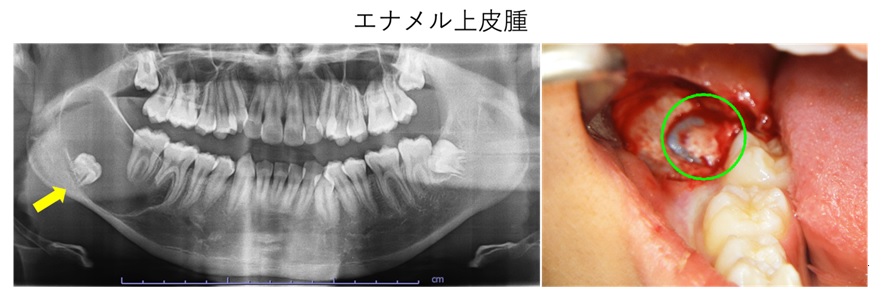

口腔腫瘍・嚢胞

口腔腫瘍は、口腔内に発生する異常な組織増殖を指します。腫瘍は良性と悪性があり、良性腫瘍は一般的にゆっくり成長し、転移しませんが、悪性腫瘍(口腔癌)は速やかに増殖し、転移する可能性があります。嚢胞は液体や半液体が入った袋状の構造で、感染や炎症、外傷が原因となることがあります。

治療法は、腫瘍や嚢胞の種類と大きさ、場所によって異なります。口腔内の異常に気づかれた場合は、ご相談ください。